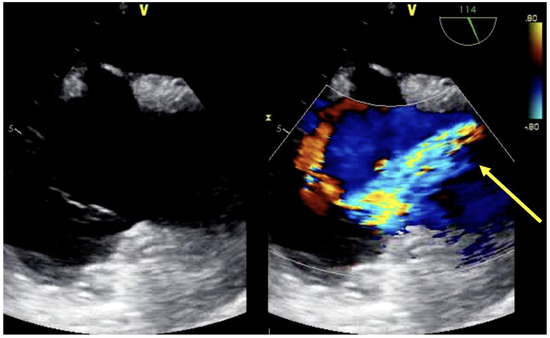

| Assessment of peripheral vasculature for size, disease, thrombus | Assessment of return (outflow) “jet” | Confirmation of cannula position |